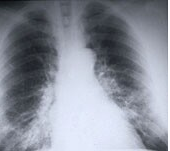

肺癌是最难治疗和最致命的癌症。非小细胞肺癌(非小细胞肺癌)是这种恶性肿瘤最常见的形式。